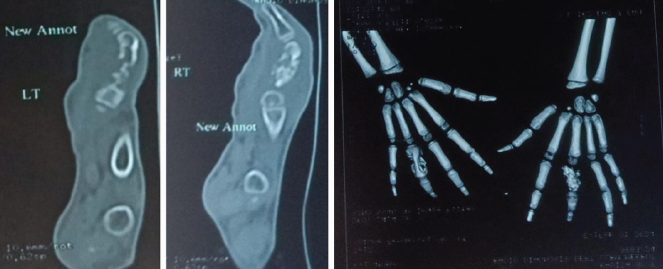

X-rays revealed cystic expansion and cortical thinning [3] of the proximal phalanges with lytic lesions (Fig. 2). Computed tomography imaging confirmed cortical destruction and periosteal reaction (Fig. 3).

Figure 3: Computed tomography radiographs.